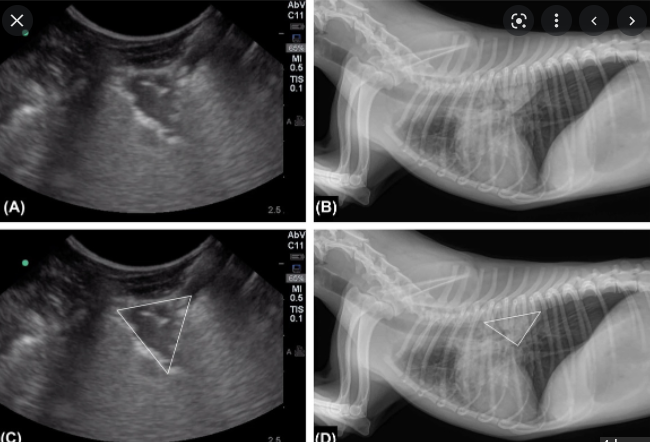

JVECC에 최신으로 나온 논문이 폐혈전증이 있는 환자에서 LUS 를 하게 되면 쐐기 모양으로 무에코성 혹은 bubble lung 이 보이는 경우가 있다는 논문이 나왔다.

하지만 이는 이 wedge가 변연에 존재할때 "이렇게 보일 수 있다" 라는 의미라고 생각해야지

이런 영상이 없기 때문에 폐혈전은 아니다, 라고 판단해서는 안된다.

오시려 이 논문에서 소중한 사진은 방사선 사진으로

폐혈전이 있는 경우 solid한 폐 영역의 국소적인 consolidation 이 특징이라는 사실을 잘 기억해야 한다.